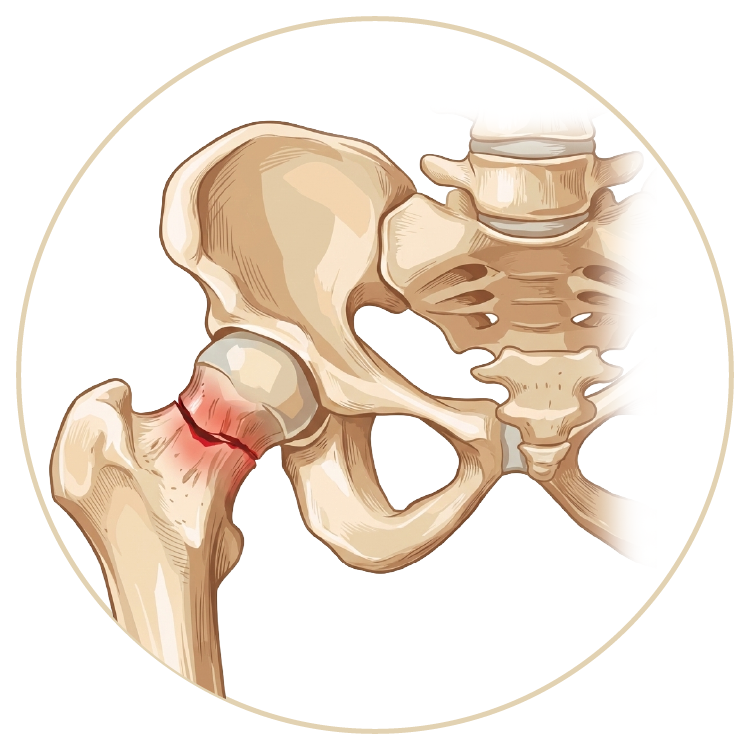

Kalça Hastalıkları ve Tedavileri

Kalça Sıkışma Sendromu

Travmatik Kalça Çıkığı